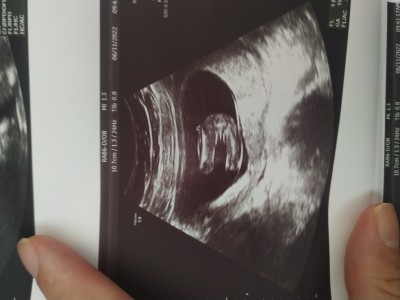

15+2 cinsiyet tahmininde bulunabilir misiniz

Gebelik haftası 15+2

Amin inşallah İlk bebeğimiz, doktor Kıza benziyor dedi ama Emin olamadı değişir mi bu haftadan sonra

Kiz  hayrli evlat olsun bacak arasindan gözüküyor

Erkek bebiş gibi Canım bacaklarının arasında eleman duruyor  :)

Kız bebek gibi geldi bana

Bacak arası boş canım %100 kız :)

14+5 de aynı görüntüyü yakaladı doktor bacak arasi bos ve kız dedi 18de yine kız dediler, 21+2 de ayrıntılı ultrason da erkek der bir başka doktor şok oldum ☺ ama cinsiyet yanılması çok oluyor 16.haftadan sonra genelde değişmez diyorlardi hala net değil benim için bi sonraki kontrolde net olur ☺

Bu hafta kontrole gittik kesin erkek dedi

Bu hafta gittik gösterdi pipisini kesin erkek dedi çok şaşırdık yine değişir mi bilmiyorum